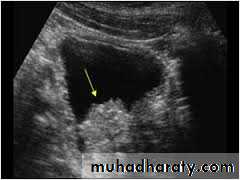

U/S : fixed massEXU : filling defect

CT & MRI : looking for LN

Cystoscopy : is the definitive method

U/S

IVP

CYSTOSCOPY